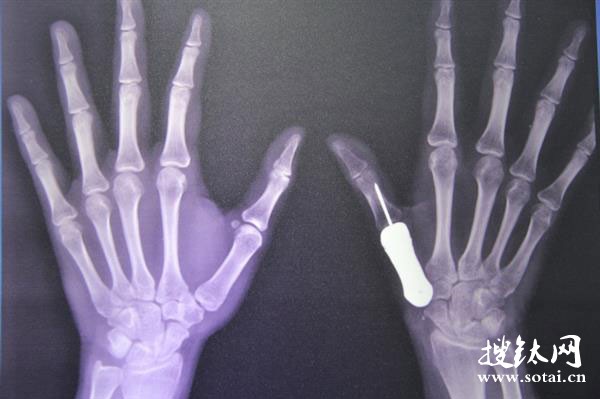

據了解,這個3D打印鈦金屬假體的制作過程是這樣的:首先,通過使用X光掃描患者的左手拇指再進行鏡像創建出右手拇指骨骼應有樣子的3D數字模型;然后,用樹脂材料做出拇指的實體模型;最后,使用生物醫療級鈦金屬做出了最終的成品。雖然整個過程耗時僅僅1周,但這種方法的開發卻耗費了該院矯形科近2年的時間。

第一階段的手術是在2015年6月進行的。當時,醫生們取出了患者已經損壞的拇指骨骼。然后,為了確保腫瘤不再復發,他們選擇了等待觀察。在3個月后的9月份確定之后,他們進行了第二階段的手術,將3D打印的鈦金屬假體植入了患者手部并且連接到了最近的肌腱上。到目前為止,患者的恢復狀況相當良好,接受手術的拇指已經可以正常活動了。